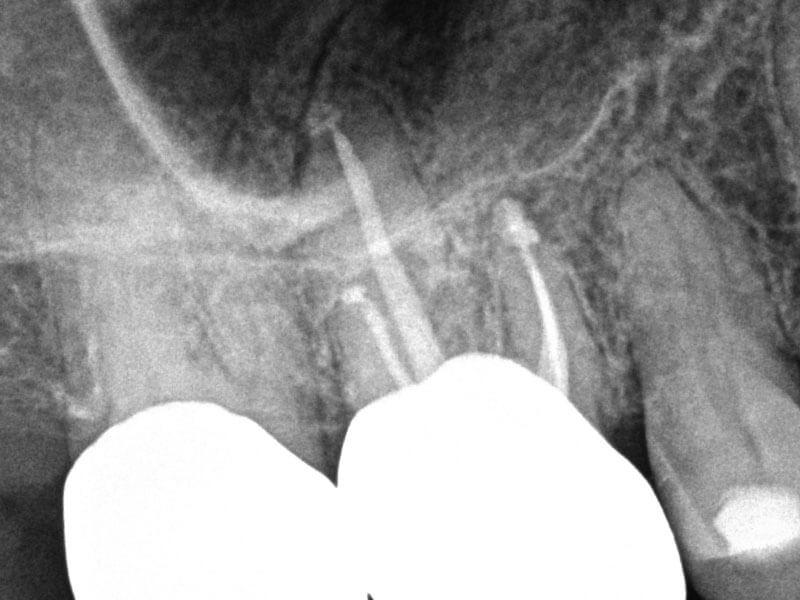

Silver Point Retreatment with Symptomatic Apical Periodontitis

74-year-old female presented with biting tenderness for five days. History of RCT 50 years ago. Clinical testing revealed Tooth #3 was tender to percussion, biting and grinding. Diagnosis: #3 previously treated and symptomatic apical periodontitis. Treatment plan: silver point retreatment #3. Accessed, removed silver points, shaped canals with ProTaper Gold®GentleWave® Procedure with ProControl™ completed. Obturated with TruNatomy® 25 GP and BC Sealer HiFlow™. BC Liner™ over orifices.

Pre

Post